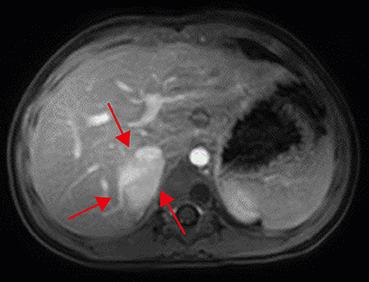

For more detailed examination, magnetic resonance imaging (MRI) was taken. An arterial T1-weighted MRI showed a lobulated mass measuring 3.6×3.8 cm, with high signal intensity, in the right suprarenal area (Fig. 2). Positron emission tomography (PET)-computed tomography (CT) showed hypermetabolism in the right adrenal gland and suggested the need to clarify whether this is a metastatic lesion at the anterior aspect of right psoas muscle (Fig. 3).

Abdominal magnetic resonance imaging. An arterial-phase imaging shows enhancing lobulated mass (multiple red arrows) in the right suprarenal area, displacing intrahepatic inferior vena cava anteriorly and suspicious of the invasion of right hepatic lobe.